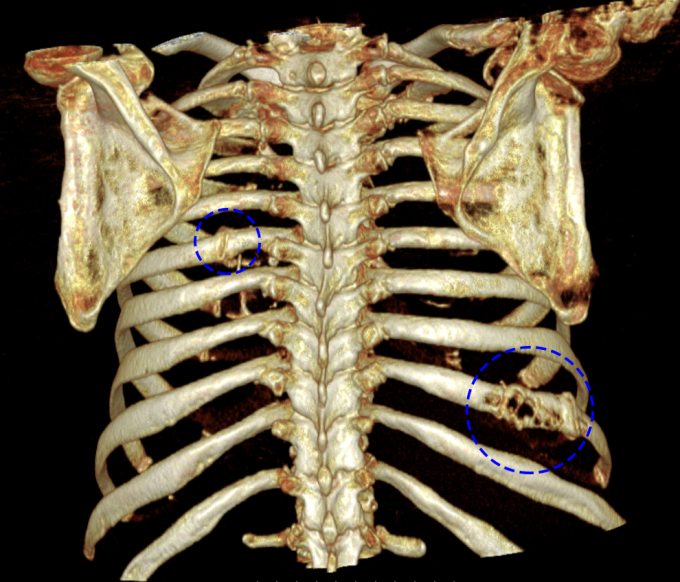

Đơn cử ông Thịnh, 81 tuổi, đau cột sống thắt lưng 3 tháng, được chẩn đoán thoái hóa khớp, khó thay đổi tư thế hay vận động. Ông đến Phòng khám Đa khoa Tâm Anh Cầu Giấy (Hà Nội) chụp cộng hưởng từ (MRI) và cắt lớp vi tính (CT) cho thấy nhiều ổ tổn thương tiêu xương, phá vỡ vỏ xương ở cột sống ngực, xương sườn và thắt lưng. Sinh thiết tủy xương xác định ông mắc bệnh đa u tủy xương.

Tổn thương tiêu xương của ông Thịnh trên phim chụp CT. Ảnh: Bệnh viện Đa khoa Tâm Anh